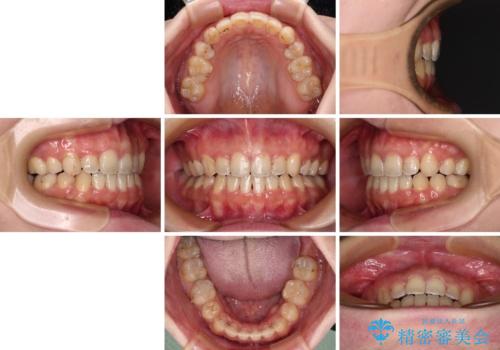

八重歯を抜歯矯正でスッキリと メタルブラケットでの矯正治療

- 八重歯と上下前歯のでこぼこを気にして来院された患者様です。

上下前歯部叢生のスペース獲得のため、上下顎左右小臼歯各1歯(計4本)と全ての親知らずを抜歯して、矯正治療を行うこととしました。

八重歯とは別に上下前歯の隙間という問題もありました。こちらは舌突出癖によるものと考えられたため、舌のトレーニングをしっかりと行っていただきました。